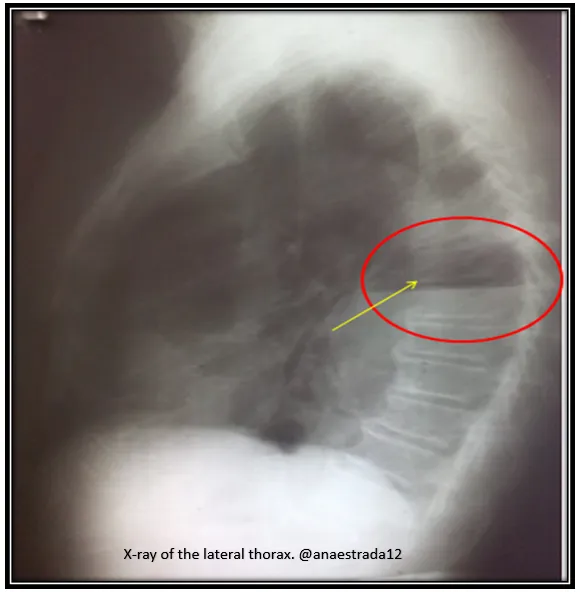

The diagnosis is confirmed by X-ray and chest CT scan (Rx Tx, TC Tx).

Where the pathognomonic sign of this entity in the chest X-ray is the presence of a cavity with hydroaeréo level.